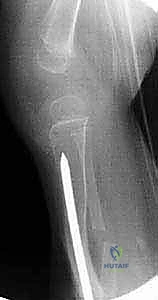

الخطوة الخامسة: إدخال قضيب ويليامز

يتم اختيار قضيب ويليامز بالطول والسمك المناسبين بناءً على قياسات دقيقة. يتم إدخال القضيب من أعلى قصبة الساق (قرب الركبة) أو من أسفلها، ليخترق القناة النخاعية، ويعبر منطقة الكسر، ليصل إلى الجزء الآخر من العظم، مما يضمن استقامة الساق وتثبيت الكسر بقوة.

الخطوة السادسة: التعامل مع عظمة الشظية

كما ذكرنا في التشريح، غالباً ما تعيق الشظية استقامة قصبة الساق. يتم إجراء شق منفصل لعمل قطع عظمي في الشظية (Fibular Osteotomy)، مما يسمح بتصحيح التشوه وتطابق نهايات قصبة الساق المكسورة بشكل مثالي.